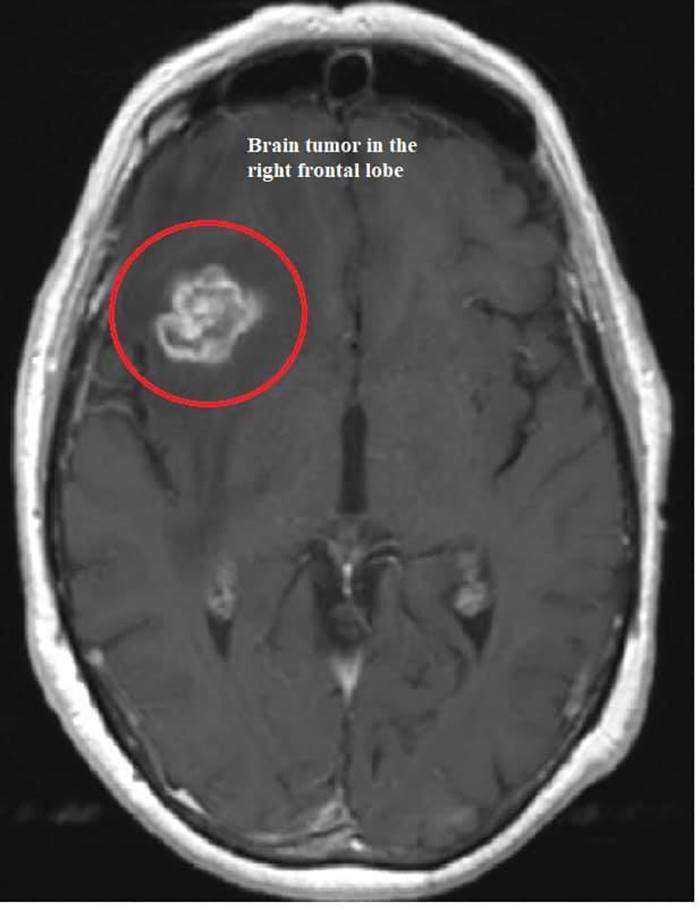

ผลสุดท้าย สแกนสมองพบเนื้องอกสมองส่วนหน้า ทำให้หมอสรุปได้ว่า

1. เนื้องอกสมองด้านหน้า สามารถเป็นสาเหตุนิสัยแปลก ๆ ที่เกิดขึ้นได้ เช่นความจำเสื่อมเร็ว พฤติกรรมเปลี่ยนไปมาก ยิ่งถ้ากลั้นปัสสาวะไม่ค่อยได้ ควรรีบพบหมอ

2. เนื้องอกถ้าไม่รุกราน ตัดทิ้ง คนไข้สามารถดีขึ้นได้ แล้วมาฟื้นฟูสมองต่อเนื่องให้กลับมาได้มากที่สุด แต่ถ้าเป็นมะเร็งเนื้อร้ายระยะรุกราน ก็ต้องรักษายาว ๆ ต่อไป